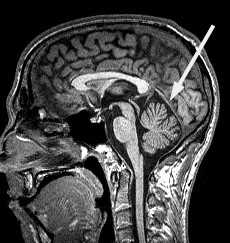

Локализация патологического очага при МРТ головного мозга начинается определения расположения очага по отношению к намёту мозжечка. Поэтому образования выше намёта относятся к супратенториальным, а все что ниже - к инфратенториальным.

МРТ головного мозга. Срединный сагиттальный срез. Намёт мозжечка (стрелка).